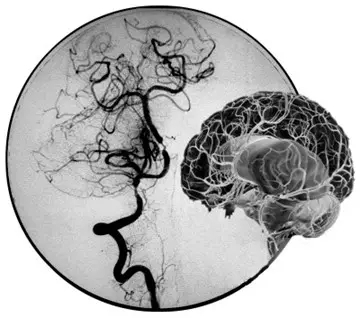

DSA圖片上提示顱底血管煙霧現(xiàn)象

“煙霧病”,原本是起源于日本的一類疾病,又稱“Moyamoya病”或“腦底異常血管網(wǎng)癥”,是一組以頸內(nèi)動脈虹吸段及大腦前、中動脈起始部狹窄或閉塞,腦底出現(xiàn)異常的小血管網(wǎng)為特點的腦血管病。因腦血管造影時呈現(xiàn)許多密集成堆的小血管影,似吸煙時吐出的煙霧,故名煙霧病。

目前明確的病因明確,跟遺傳有關(guān),可能有與后天血管的變態(tài)炎癥反應(yīng)有關(guān)。主要臨床癥狀有表現(xiàn)為“缺血性腦卒中”和“出血性腦卒中”的臨床癥狀,還可表現(xiàn)為癲癇發(fā)作。病程發(fā)作復(fù)雜多變,可反復(fù)發(fā)作并發(fā)作規(guī)律不可預(yù)測,預(yù)后較差。診斷主要可通過頭顱MRA(注:磁共振血管造影)或CTA(注:CT血管造影)確診,最能明確診斷是腦血管DSA(注:Digital Subtraction Angiography,血管造影)檢查,發(fā)現(xiàn)頸內(nèi)動脈末端及大腦前、中動脈起始端狹窄或閉塞,并見顱底出現(xiàn)明顯異常的小血管網(wǎng)。可通過手術(shù)或內(nèi)科的藥物治療,但效果欠佳,易反復(fù)發(fā)作。

提到煙霧病這個新鮮的詞匯,很多人可能要和抽煙連在一起,其實兩者根本就不相關(guān)。“之所以叫煙霧病,其實是一個形象描述大腦像煙霧狀的小血管的特征。”暨南大學(xué)附屬第一醫(yī)院神經(jīng)外科王向宇主任告訴記者,發(fā)生煙霧病時,腦內(nèi)主要血管會因各種不明確原因(如遺傳、感染、血管炎、青少年動脈粥樣硬化、放射治療等)變得狹窄甚至阻塞,導(dǎo)致腦缺血。這時大腦為了拯救因缺血而逐漸枯萎的神經(jīng)元,就會從已經(jīng)變狹窄的大血管上生出小血管來緩解缺血狀況,這些小血管交叉成網(wǎng)狀,一旦做數(shù)字剪影血管造影檢查,醫(yī)生就會發(fā)現(xiàn)像吸煙時噴出的煙霧狀血管網(wǎng),為此稱為“煙霧病”。